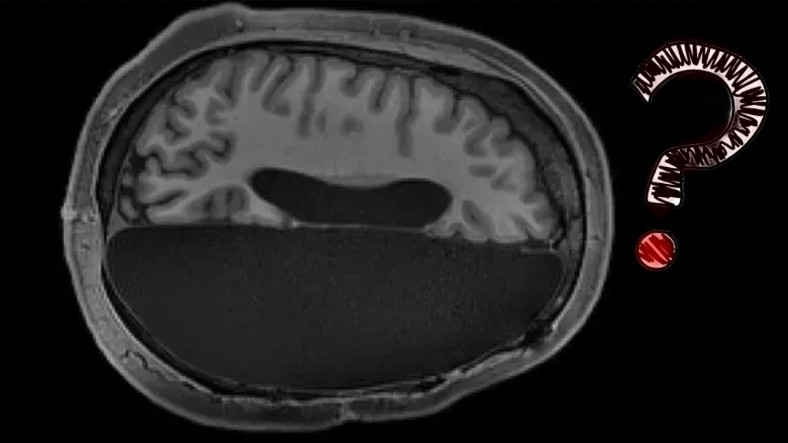

Beynin yarısından alınan bir insan, yaşama normal bir şekilde devam edebilir mi? Bu cevaba cevap için California Teknoloji Enstitüsü’nün araştırmasına göz atmak gerekiyor.

California Teknoloji Enstitüsü’ndeki, beynin yarısı olmayan bu 6 kişinin MRI (manyetik rezonans görüntüleme) sonuçları incelenerek, sağlıklı insanların MR sonuçlarıyla karşılaştırdı.

Yapılan incelemenin sonuçları birden fazla şaşırttı! Radyolojik görüntüler referansları; yarım beyinle yaşamlarına devam eden bu 6 kişinin beyin faaliyetleri ile sağlıklı insanların beyinlerini yürütmek arasında büyük ölçekli gösterim olduğu görülmüştür.

Yani yarım beyinle yaşamak mümkün!

beyindeki sağlıklı bölge, hasret gören Yarım küredeki nöron ağlarının eksikliğini belli bir oranda telafi edebilmek için ağ akışını artırmaya çalışıyor.